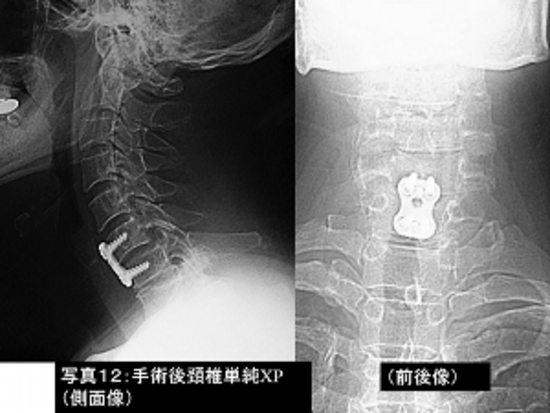

写真12:写真11の患者さんの手術後の頚椎単純レントゲン撮影像です

。